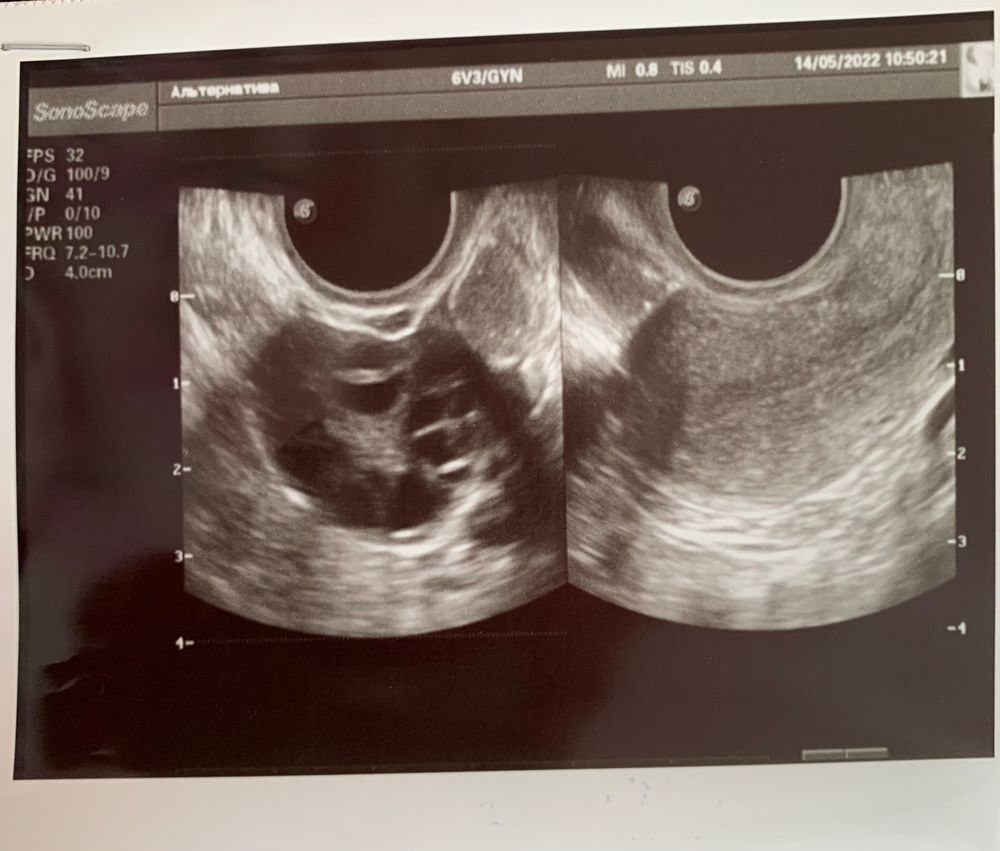

Сходила сегодня повторно на УЗИ, но картина не поменялась, только кол-во фолликулов стало больше 10 😐 Стала вести график БТ, который как раз подтверждает то, что у меня все ещё 1-я фаза (66-й ДЦ). Очень жду приёма с врачом🙏🏻